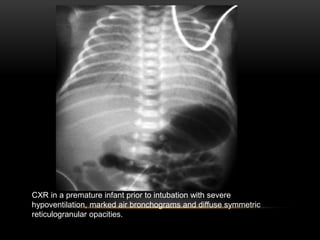

• The classic radiographic findings of RDS include

a) diffuse symmetric reticulogranular densities,

a) prominent central air bronchograms and generalized hypoventilation.

4. Respiratory Distress Syndrome (RDS)

CXR in a premature infant prior to intubation with severe

hypoventilation, marked air bronchograms and diffuse symmetric

reticulogranular opacities.